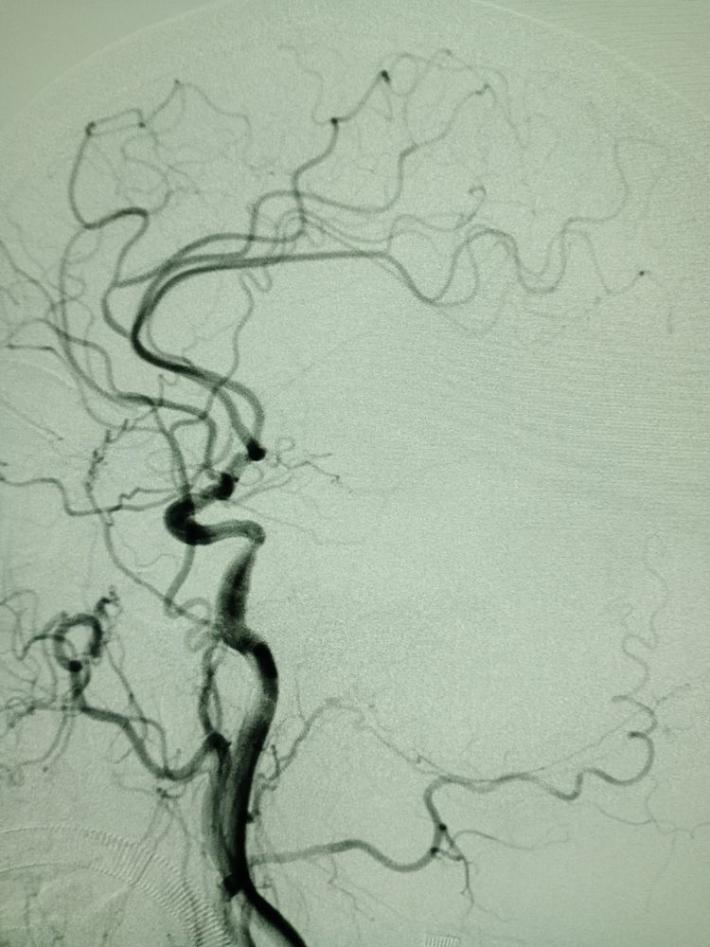

右侧颈总动脉造影提示:右侧颈内动脉颅内段慢性闭塞,非责任病变。

左侧颈总动脉造影提示:左侧大脑中动脉闭塞,考虑责任病变。